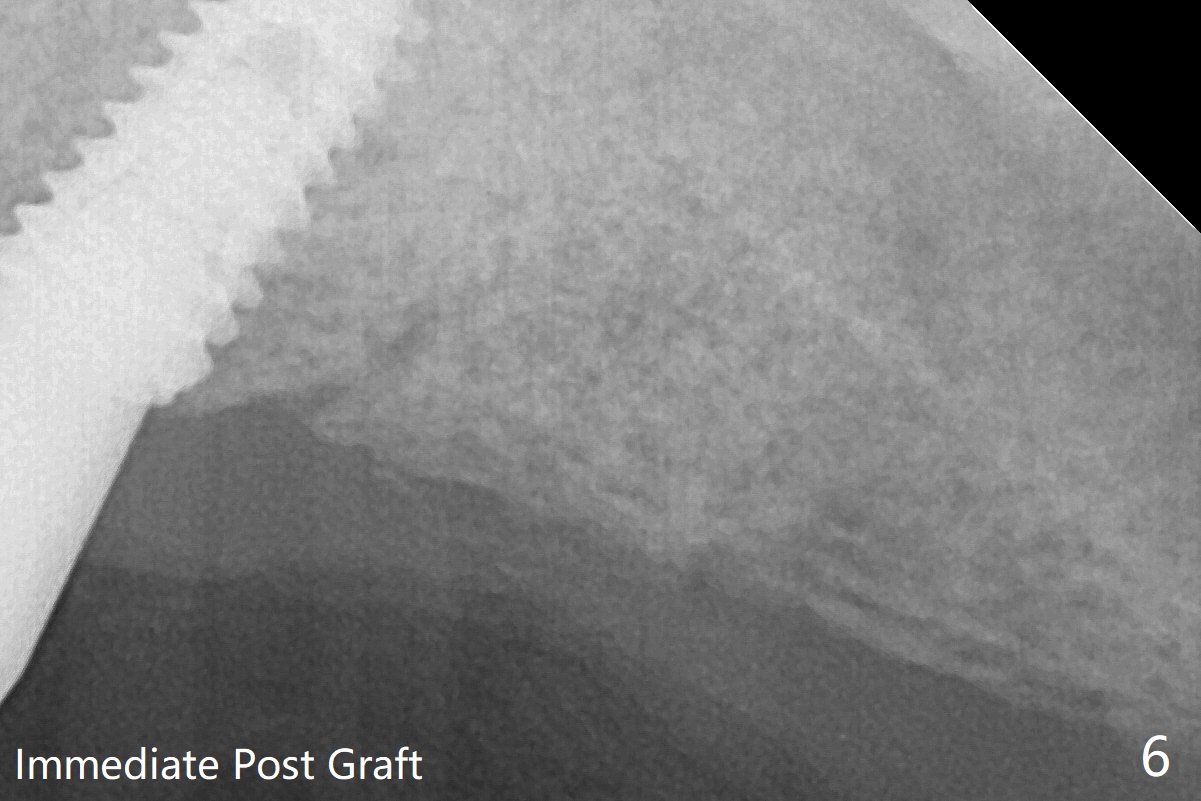

The pattern of bone graft changes 3 months postop (Fig.7, as compared to Fig.6).